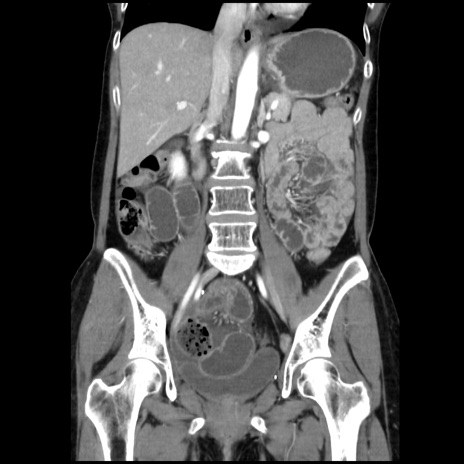

症例32(冠状断像)

【症例】40歳代 女性

【主訴】上腹部痛、嘔気・嘔吐

【現病歴】約9時間前頃から急に上腹部痛、嘔気、嘔吐が出現。改善しないため救急要請。

【既往歴】子宮頚癌(広汎子宮全摘術、放射線療法)、腸閉塞

【身体所見】腹部:平坦、軟、腸雑音亢進、上腹部を中心に腹部全体に圧痛あり。

【データ】WBC 8400、CRP 0.03